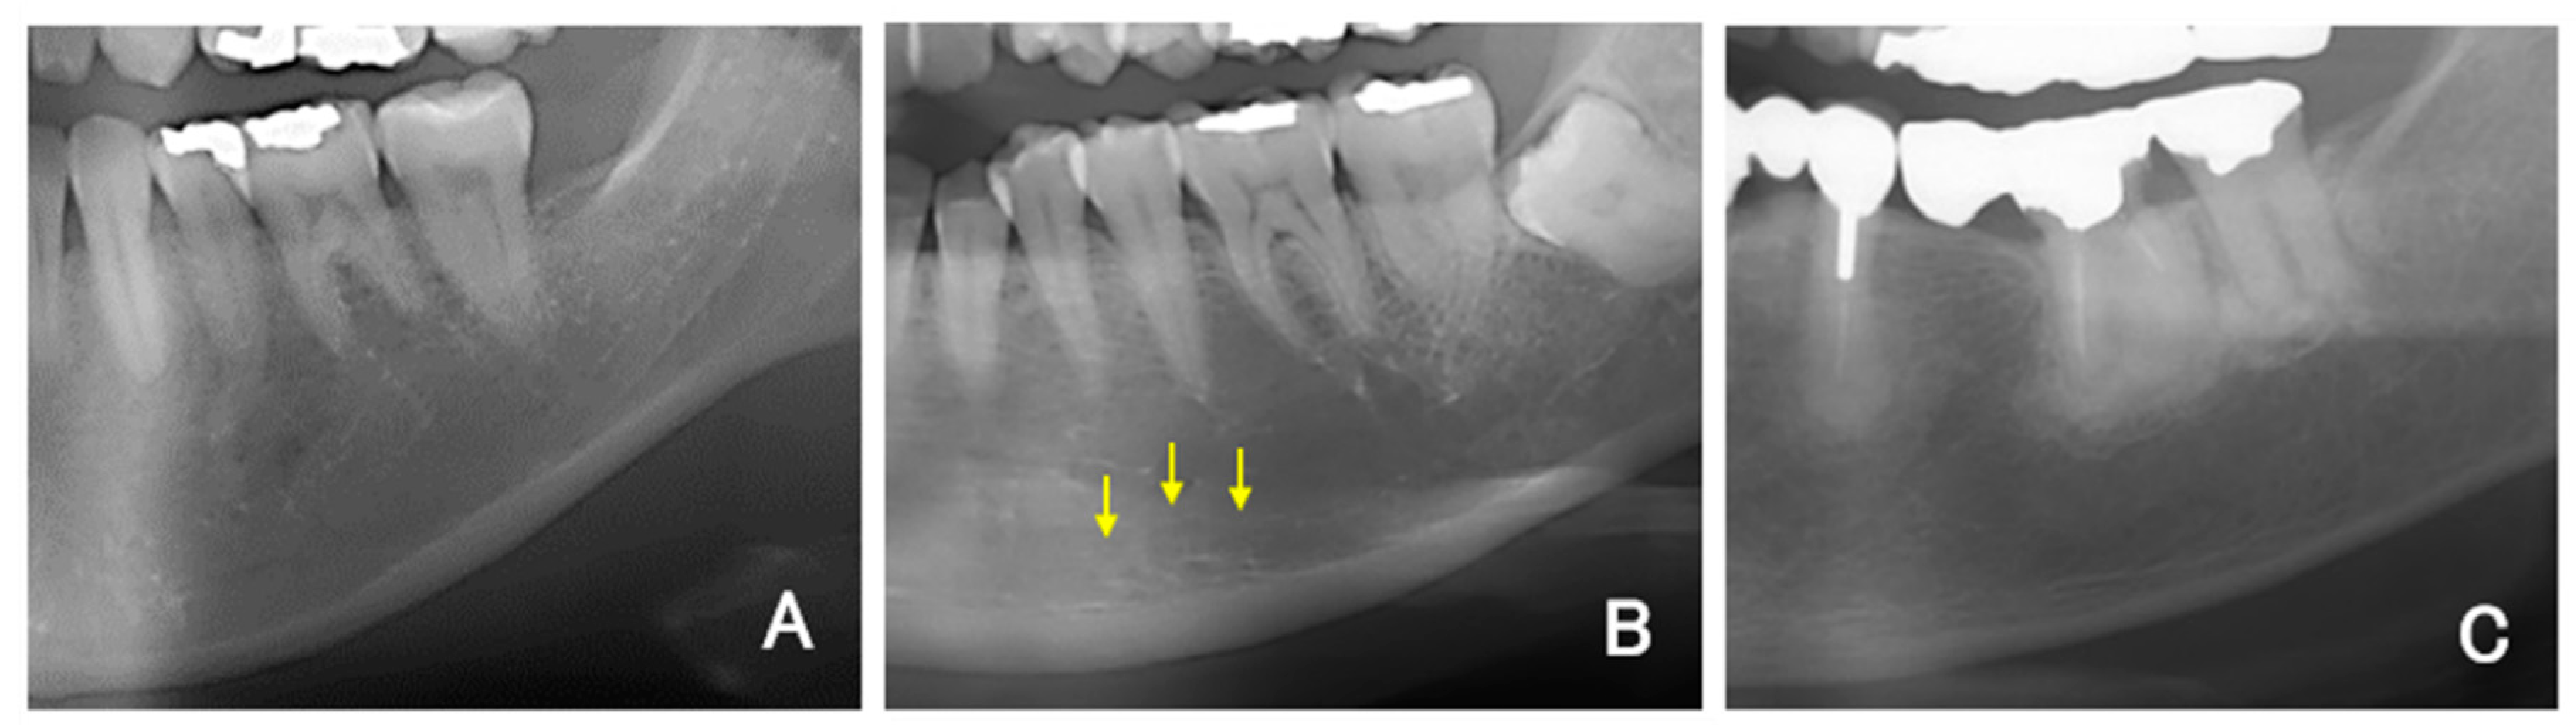

For all DPR images, the mandibular inferior cortical bone morphology was classified into three types according to a report by Klemetti and Kolmakow [17]. Class 1 (C1) has a smooth inner surface of cortical bone, class 2 (C2) has an irregular inner surface of cortical bone with linear resorption, and class 3 (C3) has severe linear resorption and cortical bone rupture over the entire cortical bone (Figure 1A–C). Diffuse opacities, such as sclerosing osteomyelitis that did not correspond to any of the above types, were recorded separately. Two sites on the left and right sides were evaluated and recorded per patient. Therefore, 140 sites in the DPR images were covered. The MCI was assessed twice by dentists (K.S., a periodontist; T.Y., an oral surgeon; and Y.A., a dental trainee) who had been trained in classification, and the second assessment was used. The classification result was replaced with a numerical value, such as 1 for C1, 2 for C2, and 3 for C3, and the averages of the three examiners’ values were rounded to obtain the final MCI (e.g., if the mean value was 1.66, then it was classified as C2).

Figure 1. A) Representative example of C1. (B) Representative example of C2. Multiple upper marginal lines of the mandibular inferior cortical bone were identified and obscured (arrows). (C) Representative example of C3.